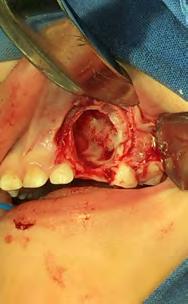

Bajo anestesia general, se realizó la escisión quirúrgica de la lesión, junto con la extracción del canino superior izquierdo de la primera dentición impactado. El tumor era de color marrón y medía aproximadamente 50 × 13 mm.

La muestra se envió para análisis histopatológico (Figura 3).

Se llevó a cabo la intervención quirúrgica bajo anestesia general con una intubación nasotraqueal (protocolo completo que se maneja en la Unidad de Especialidades Odontológicas. SEDENA), se procedió al acto quirúrgico siguiendo los protocolos, antisepsia del campo y colocación de compresas según técnicas, se inició, previa anestesia local con lidocaína al 2% con epinefrina 1:100,000 diseñando un colgajo de Newman parcial para levantar un colgajo mucoperiostico de espesor total de tipo axial mucoperiostico (Figura 4A)

Se realizó la osteotomía, después de exponer la masa tumoral con instrumental de rotación de alta velocidad con fresa 702 con abundante irrigación, se seccionó la masa tumoral y con el objetivo de no lesionar estructuras anatómicas vecinas y en relación con la lesión, se levantó la cortical ósea con legra y se accede a la lesión, de forma controlada y progresiva (Figura 4B).

Figura 4. A-E. Secuencia técnica quirúrgica.

Se realizó la escisión completa de la masa tumoral, mediante curetaje; se extrajo el órgano dentario 63, y se enucleo el tumor, el cual fue enviado a estudio histopatológico, los múltiples dentículos fueron extraídos hasta limpiar el lecho quir ú rgico por completo, se alisaron aristas de hueso con pieza de mano de alta velocidad y lima para hueso, se lavó con suero fisiológico y se procedió a suturar (Figura 4C-4E).

En el análisis microscópico se identificó una lesión compuesta por nidos y cordones de células de epitelio odontogénico con diferenciación ameloblástica inmersas en un tejido fibroso moderadamente celular con zonas de esclerosis junto a focos de depósito cementario, dentinarios y trabéculas óseas adyacentes. Diagnóstico histopatológico: fibrodentinoma ameloblástico (Figura 5).